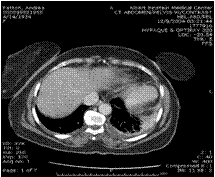

45 yo presents with LUQ pain